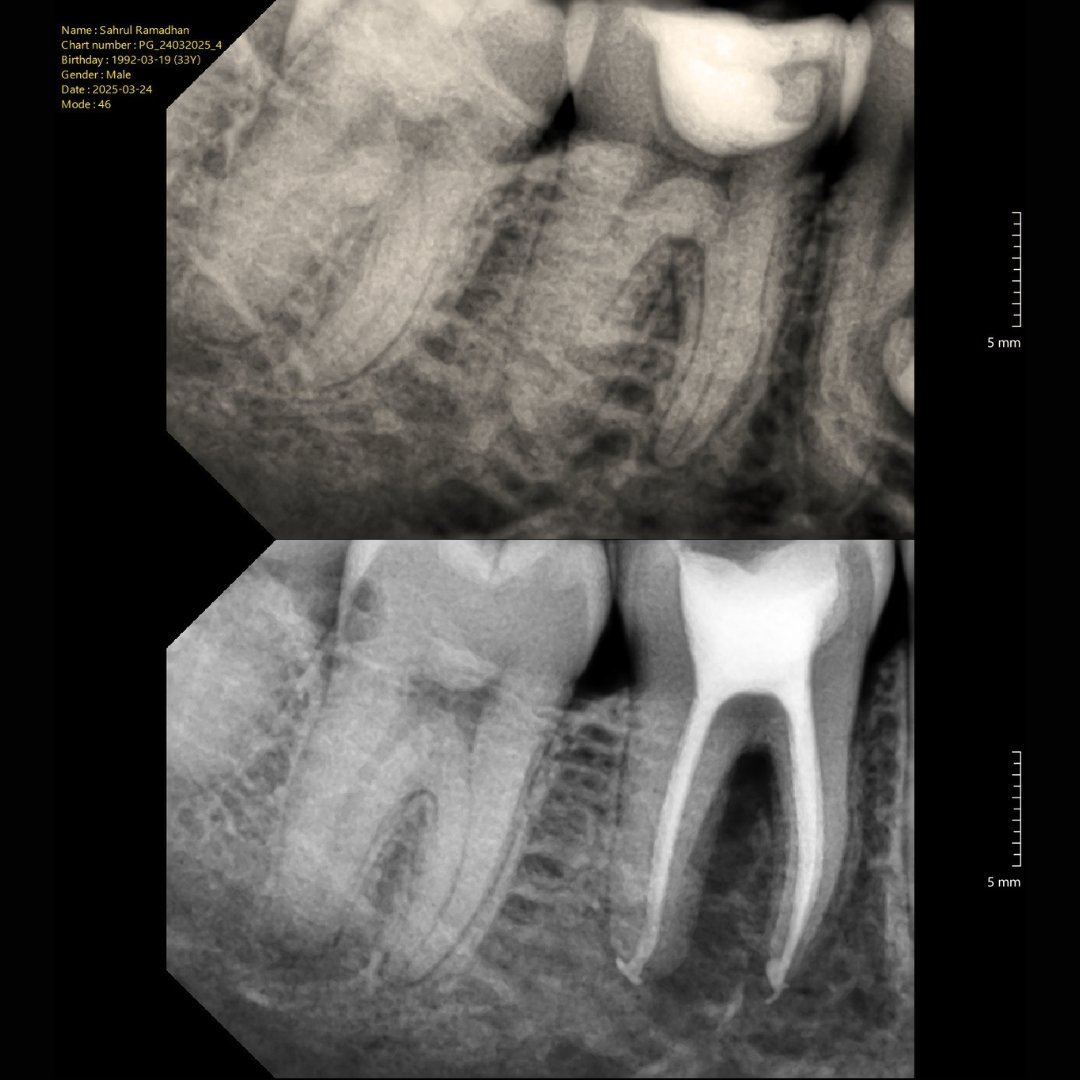

Before After Perawatan Saluran Akar (PSA) di Klinik Utama Pondok Gigi Jakarta

Transformasi nyata setelah perawatan saluran akar (PSA) di Klinik Utama Pondok Gigi Jakarta. Dari gigi rusak dan nyeri hingga kembali sehat dan berfungsi normal. Dikerjakan oleh dokter gigi profesional dengan teknik endodontik modern dan alat berteknologi tinggi untuk hasil maksimal.